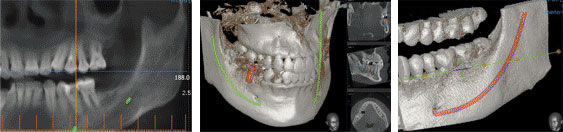

以0.1mm的单位来测量,鄂骨的厚度.长度.神经线的位置等详细的信息,可以观察整体鄂骨的状态,能精确的测出突出部位.轮廓厚度等。因此可以预测术后求美者较理想的脸型。

一般的X-射线只能确认神经线的大概位置和牙根部的位置,无法确认神经线准确位置的缺点。而三维CT是通过准确的找出神经线的部位,测量神经组织的单位达到mm,因此大大的减少神经.肌肉等组织的损伤。

一般脸骨矫正是通过很小的切口来施术,因此手术中视野很窄。较小化的剥离才能有助于消肿,但很难确定骨的厚度.形状.靠里边的位置.神经线的位置等。为了看清楚把切口打开的话消肿和恢复都比较慢。通过三维CT(3D CT)的三维图片,在手术中能够准确的测出骨的正侧面的厚度,突出部位。所以这是整脸型手术目前较安全的方法。